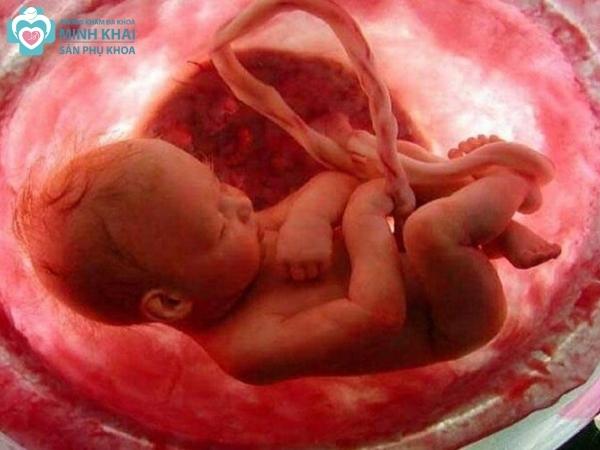

Ngay từ những ngày đầu tiên của thai kỳ, mẹ bầu sẽ được bác sĩ khuyến khích sử dụng kỹ thuật siêu âm thai 2D. Nó sẽ tái hiện lại được cấu trúc của bào thai qua bức hình đen trắng theo nguyên lý chỗ có mô cơ thể càng đặc thì màu xám trắng càng đậm. Từ đó, người mẹ có thể biết được số lượng bào thai, khảo sát vị trí đậu thai trong hay ngoài tử cung, các chỉ số sinh trắc học (tuần tuổi, kích thước,...) của thai nhi.

Kết quả siêu âm 2D cũng báo hiệu được những bất thường trong thai kỳ của người mẹ liên quan đến buồng trứng, tử cung. Ngoài ra phương pháp siêu âm này còn cho phép đánh giá được toàn diện sự hình thành và phát triển của thai nhi qua theo dõi độ lớn vòng đầu, kích thước xương đùi cũng như phát hiện sớm những dị tật bẩm sinh như bệnh down, hở hàm ếch, sứt môi, tay chân dính liền,...

Siêu âm thai 3D cho phép thấy được hình ảnh chụp thật 3 chiều của em bé chứ không phải chỉ là những mặt cắt như 2D. Không chỉ vậy hình ảnh 3D còn được chụp với các góc độ khác nhau. Nó cho thấy rõ được toàn bộ cấu trúc thai nhi chi tiết đến từng đường nét cũng như nội soi rõ các mô nội tạng, tim, hệ mạch máu,...